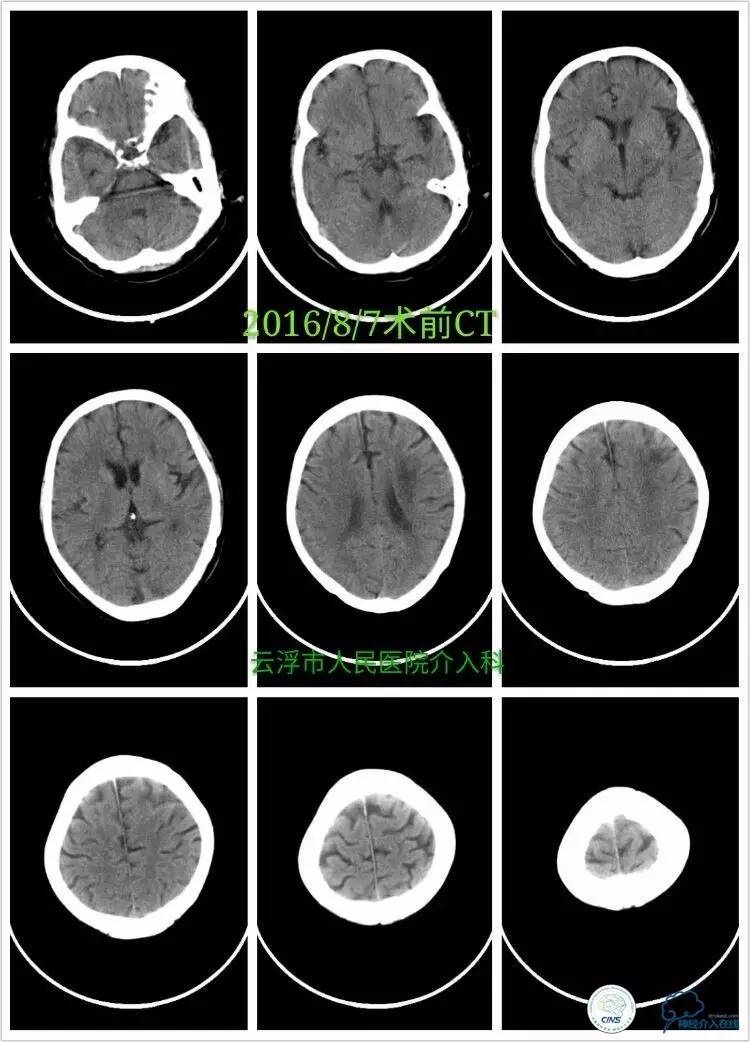

》术前颅脑CT平扫:

》2016-08-08

》术后第6小时复查颅脑CT:

》术后第四天颅脑CT: